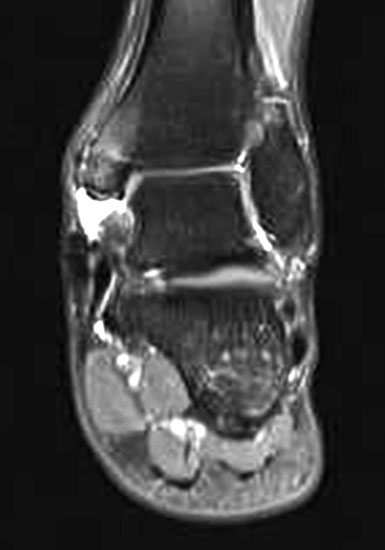

Aufgrund der geringen Zuverlässigkeit der klinischen Untersuchung und der konventionell radiologischen Bildgebung ist die Bildgebung der Wahl die Kernspintomographie (Szeimies 2014). Allerdings bestehen auch bei der Kernspintomographie klare Grenzen, vor allem hinsichtlich der Beurteilung der mechanischen Stabilität. Zuverlässige Aussagen sind möglich zum Ausmaß der Verletzung, insbesondere welche Bandanteile betroffen sind, sowie zu Begleitverletzungen. Chun et al. 11 berichteten über eine Sensitivität von 84% und eine Spezifität von 93,5% für Läsionen des Deltabandes im MRT. Befunde im MRT umfassen eine flächige Ödematisierung und Einblutung entlang des Deltabandes, meist unter Aussparung der kräftigen Pars tibiotalare posterior. Ein gewellter Verlauf, sowie eine Unterbrechung der Kontinuität der Faszikel sind Zeichen eines strukturellen Schadens. Teilweise finden sich Knochenkontussionsödeme, aber auch kortikale Absprengungen am lateralen Talusrand, der Talusschulter und am Außenknöchel. Fast immer findet sich ein Gelenkerguss (Abbildung 4).